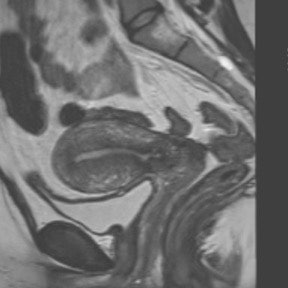

Endometriosis patients may be assessed with pelvic MRI at any time -- even during menstruation, according to a new study in the European Journal of Radiology. The researchers found no differences in the conspicuity, size, or extent of endometriotic disease at any point in a woman's cycle.

The small, prospective trial compared pelvic MR exams during menses and midcycle in women with laparoscopically proven endometriosis or a high clinical suspicion of deep infiltrative endometriosis. The research team, led by Dr. Elissa Botterill, a consultant radiologist from the radiology department at Austin Health in Heidelberg, Australia, found there was no difference in pelvic MR scans on either menstruating or nonmenstruating women (EJR, 6 August 2015).

Endometriosis is a common disease affecting women of childbearing age, with an estimated prevalence between 5% and 15%. Pelvic MR is often used in the preoperative assessment of endometriosis, as it provides an excellent overview of disease extent and is highly accurate.

Clinical assessment of endometriosis is optimally performed during menstruation, as it is thought the disease is more active and implants are more likely to be large and tender, according to the study authors. However, the optimal timing for pelvic MRI to assess endometriosis is uncertain.